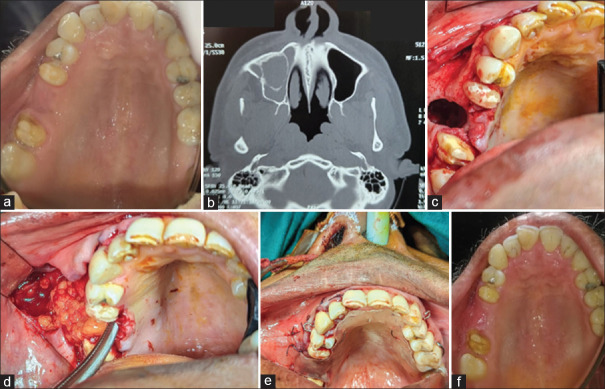

Rationale: This case series evaluates the effectiveness of the buccal advancement flap and buccal pad of fat for treating oroantral fistula (OAF) in uncontrolled diabetic patients, focusing on healing, complications and success rates.

Patient concern: OAF is a condition marked by abnormal communication between the oral cavity and maxillary sinus, often leading to infections, purulent discharge, nasal regurgitation and discomfort. Diabetic patients face additional healing challenges.

Diagnosis: OAF is commonly caused by posterior maxillary teeth extractions with symptoms exacerbated by chronic sinus infection, especially in uncontrolled diabetics.

Treatment: Two surgical techniques were employed: the buccal advancement flap and buccal pad of fat. Both aim to enhance fistula closure and minimise complications in diabetic patients.

Outcomes: Both approaches achieved successful fistula closure with satisfactory healing despite the patients' impaired healing capacity.

Take-away lessons: Buccal advancement flap and buccal pad of fat provide effective and reliable solutions for OAF management in uncontrolled diabetic patients.